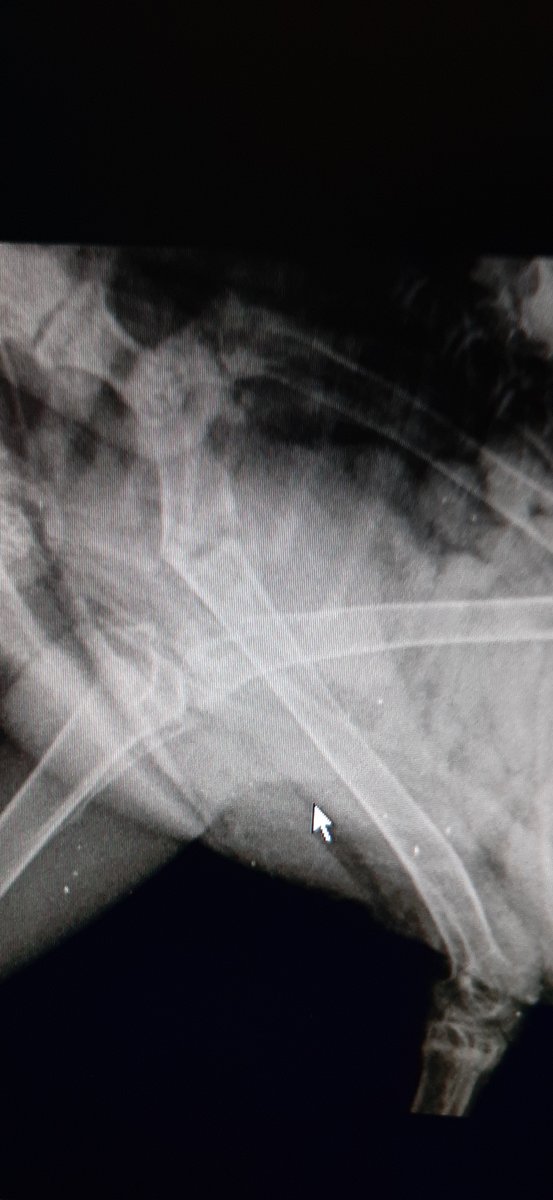

Сделала рентген.(если плохо видно,то могу попросить у вета огиринал перекинуть).Местный ветеринар сказал,что кость почти срослась и всё нормально должно быть в будущем.

20200603_185110.jpg